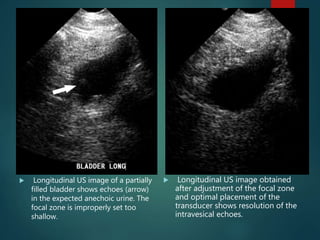

 Clinically, beam width artifact may be recognized

when a structure that should be anechoic such as the

bladder contains peripheral echoes.

 If this artifact is recognized during scanning, image

quality may be improved by adjusting the focal zone

to the level of interest and by placing the transducer at

the center of the object of interest

 Adjusting the focal zone and

placing the object of interest within

the center of the focal zone will

eliminate the misplaced echoes on

the display

 Longitudinal US image of a partially

filled bladder shows echoes (arrow)

in the expected anechoic urine. The

focal zone is improperly set too

shallow.

 Longitudinal US image obtained

after adjustment of the focal zone

and optimal placement of the

transducer shows resolution of the

intravesical echoes.